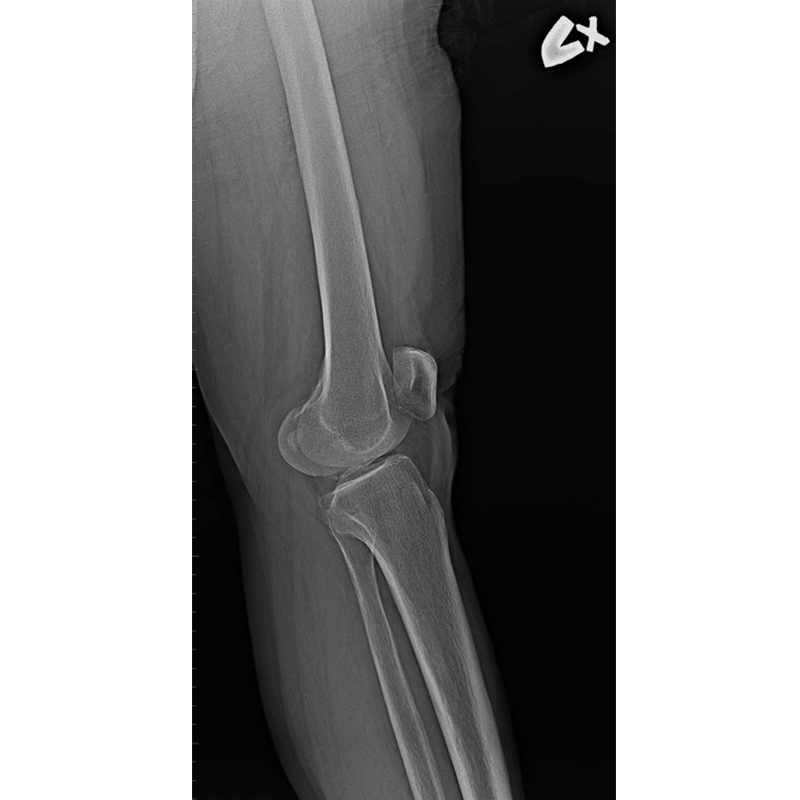

傳統部分膝置換 首頁 案例分享 膝關節手術 傳統部分膝置換 殷女士 65歲 術前 術後 張女士 71歲 術前 術後 蔡女士 74歲 術前 術後 張女士71歲 術前 術後 翁女士70歲 術前 術後 劉女士 80歲 術前 術後